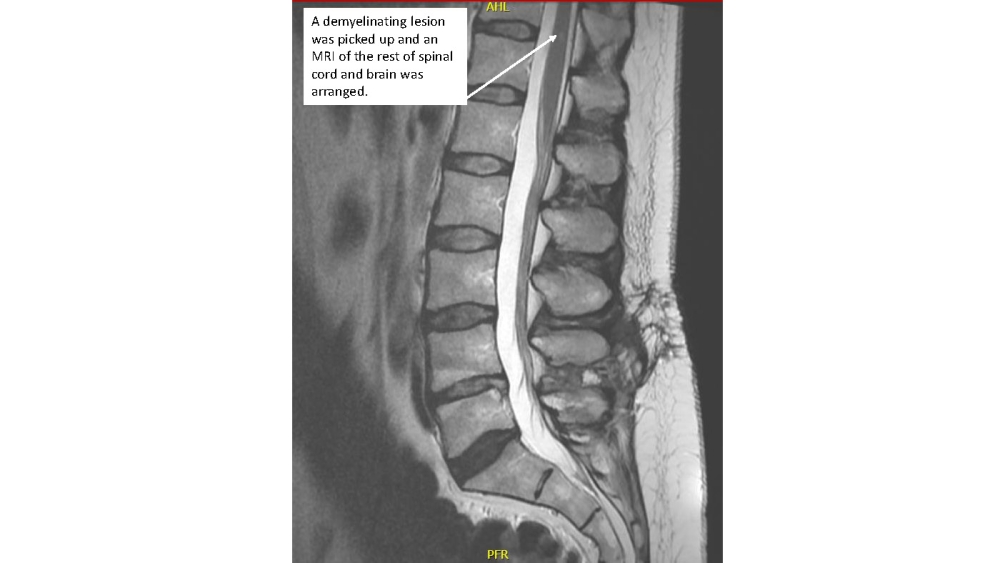

A 35 year old lady presented with severe onset back and bilateral radicular leg pain, left leg worse affected than the right. She also reported urgency of micturition and some weakness of the left leg. On examination she had signs suggestive of a lumbar disc prolapse.

- She went on to have an MRI scan of the lumbar spine

Look at the MRI scan of the rest of the spine and brain – what can you see?

- What is the likely diagnosis?

- What is your next course of action?

- What other tests are likely to be done?